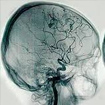

Enfermedad de Moya-Moya

Esta enfermedad fue originalmente descrita en Japón, debido a la imagen que se observa en la angiografía cerebral en forma de humo o niebla (en japonés moyamoya significa humo o niebla). Esta disposición de las arterias se debe a una oclusión progresiva de las arterias principales del cerebro, por lo que en un intento de mantener el flujo sanguíneo cerebral se forman están nuevas pequeñas arterias colaterales que en el estudio se observan como fumarolas de humo o niebla.